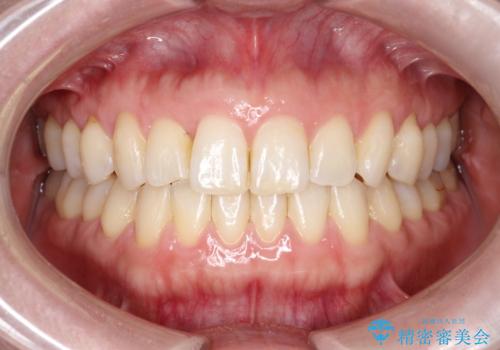

【モニター】犬歯のクロスバイトを目立たないワイヤー装置で